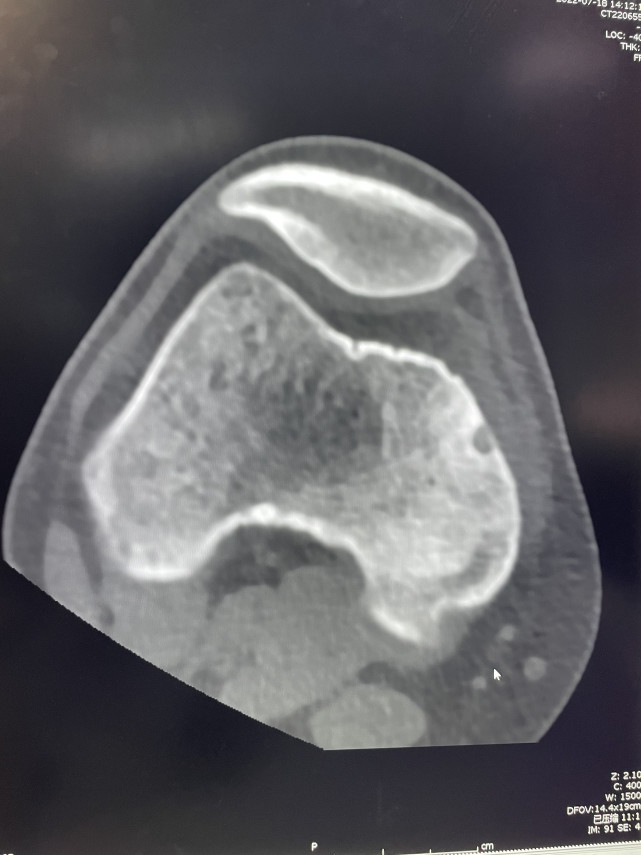

骨病肿瘤科杨团民主任接诊后,查看了X线影像并未发现明显异常。考虑到患者病史较长,持续性疼痛,杨团民主任随即让患者进行右膝关节CT检查,结果发现右股骨内髁骨皮质约4mm微小肿瘤,详细了解病史并结合症状和影像考虑为骨样骨瘤。

术中O型扫描肿瘤影像